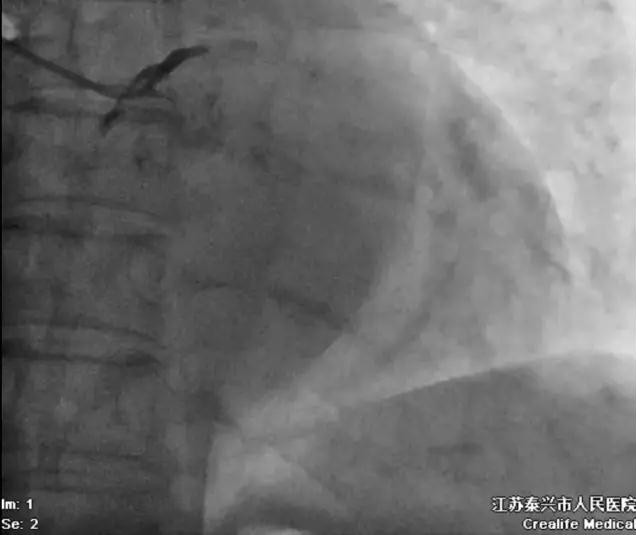

上)冠状动脉造影证实是左主干急性闭塞,术前心电图表现见上图。